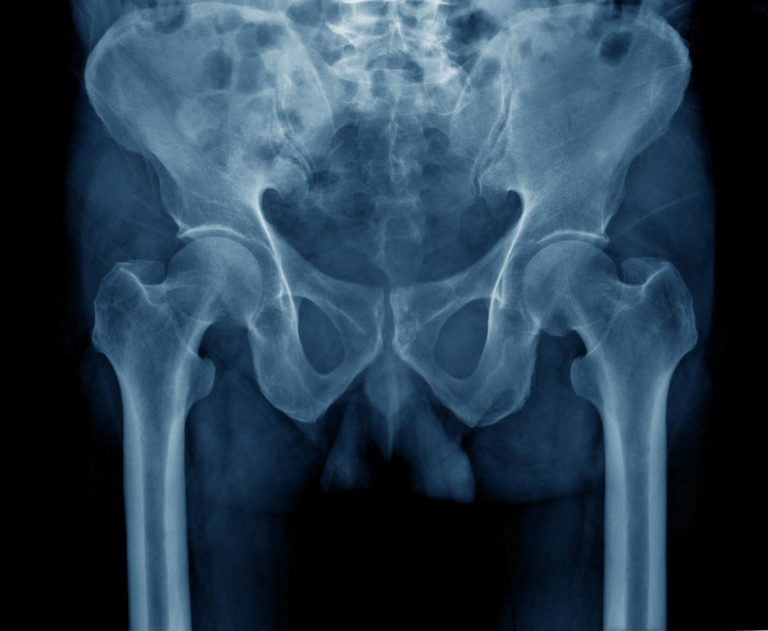

Zimmer Hip Replacement Attorney in Florida

Zimmer Hip Replacement Attorney in Florida Is There A Recall On Zimmer Hip Replacements Read about litigation involving the zimmer durom cup and m/l taper hip. Learn why the implants were recalled, case details, and. Zimmer biomet will phase out sales of its cpt hip system by december due to concerns about the risk of thigh bone fractures,. The fda is getting the word out regarding a recall effort from zimmer biomet related to. Is There A Recall On Zimmer Hip Replacements.